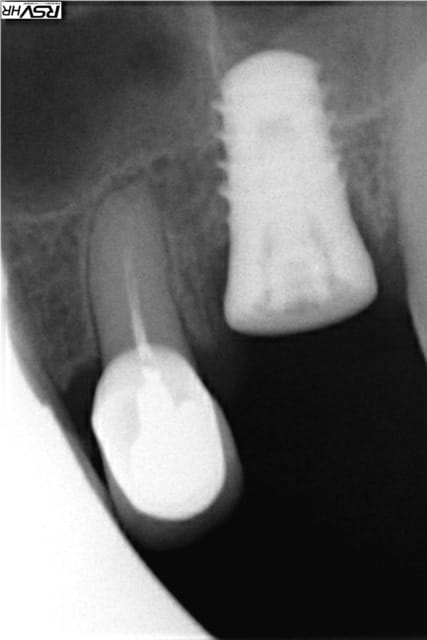

Pour Cyanolit des photos de swish plus pose en 2014

MEG1 MEG2 CH1 CH2et swiw + ric en 2015 (swish d'implant direct

2 radios de 2 zimmer SPAT1 en 2010 pose et provisoire

et SPAT2 2015 comportement actuel